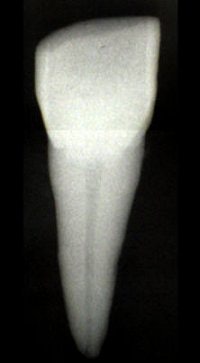

![]() |

| Kvaal's technique examines the relationship between chronological age and the 2D dental pulp size, including length and width, in individuals older than 20. Images courtesy of Dr. Guy Willems. |

In an e-mail interview with AuntMinnie.com, co-author Dr. Guy Willems -- who, along with Bosmans, is from the university's department of forensic odontology -- explained that panoramic x-rays offer some advantages over standard, long-cone periapical radiographs.

"(Panoramic x-rays) are more commonly taken, and it would take only this (one) radiograph to visualize all the teeth you need," he said.